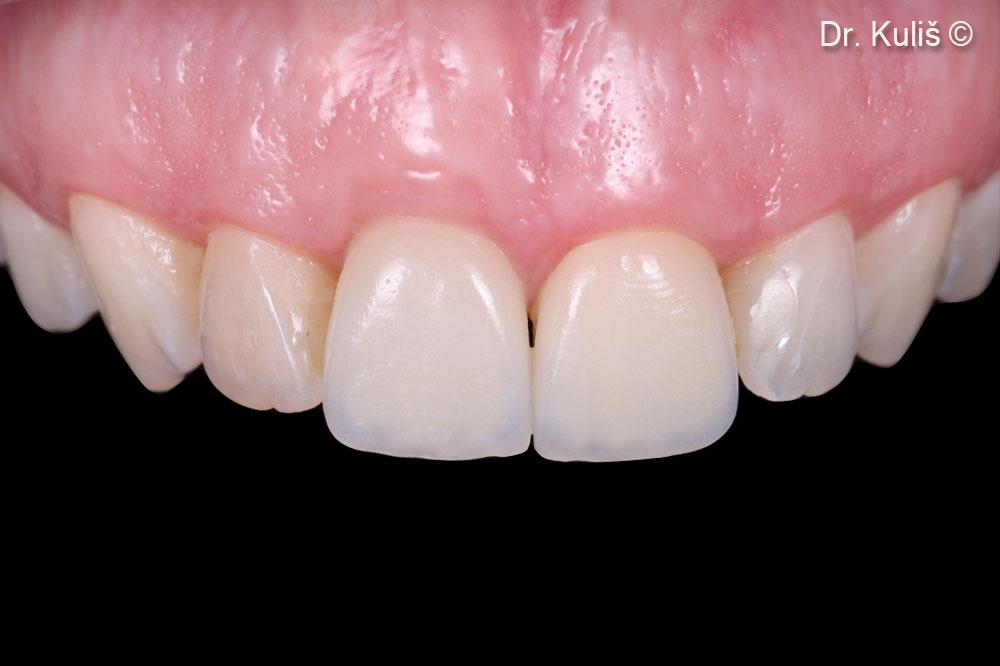

Kết quả cuối cùng sau 6 tháng kể từ khi đặt phục hình toàn sứ hoàn chỉnh.